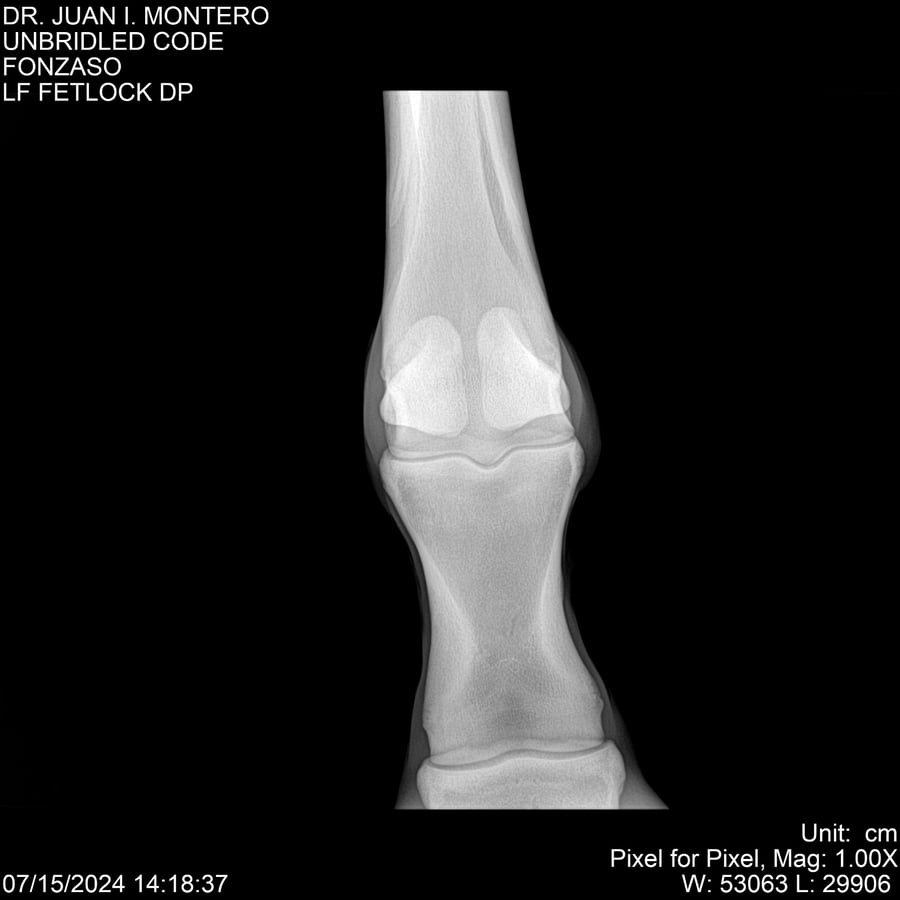

• Empresa: Abelenda N. R., Walter Hugo